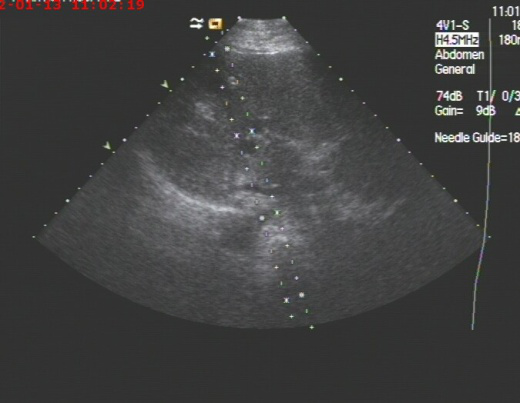

2019年10月呼吸科收治一男性、83岁高龄肺炎合并巨大肝脓肿患者,病人高烧不退,各项感染指标超高,病人既往是多囊肝病人,于10月17日进行超声引导下巨大肝脓肿抽吸治疗术。超声检查局部肝脓肿测量内经达:14cm,术中抽吸灰白色脓液800ml,并送培养,经一个多小时抽吸注药,直至抽出液体清亮,脓肿完全缩小,当即病人病情缓解,高烧消退。送检后显示感染细菌为克雷白氏杆菌,一周后原脓肿再次穿刺治疗,抽出囊液400ml,再次冲洗治疗,经培养已无细菌,随后痊愈出院。

我科开展肝脓肿、胆囊脓肿合并肝脓肿穿刺抽吸及置管术几年来,已治愈多例因高龄无法手术者,或术前减压治疗,后期再进一步手术者,经超声引导下囊肿治疗术已广泛应用于临床,因其具有不用开刀、局部麻醉、安全、痛苦小、疗效好、并发症少等特点,已成为各种囊肿治疗的首选。

通常小囊肿可以观察,但囊肿较大,超过5 cm 且有不适时,则需考虑治疗。目前介入治疗是最为有效的治疗手段,我们在彩超的引导下,进行穿刺,可以有效避开血管,选择最佳路径,经过反复注射无水酒精再抽出就能达到治愈的目的。该项技术对于全身各部位囊肿,尤其卵巢巧克力囊肿效果也非常好。